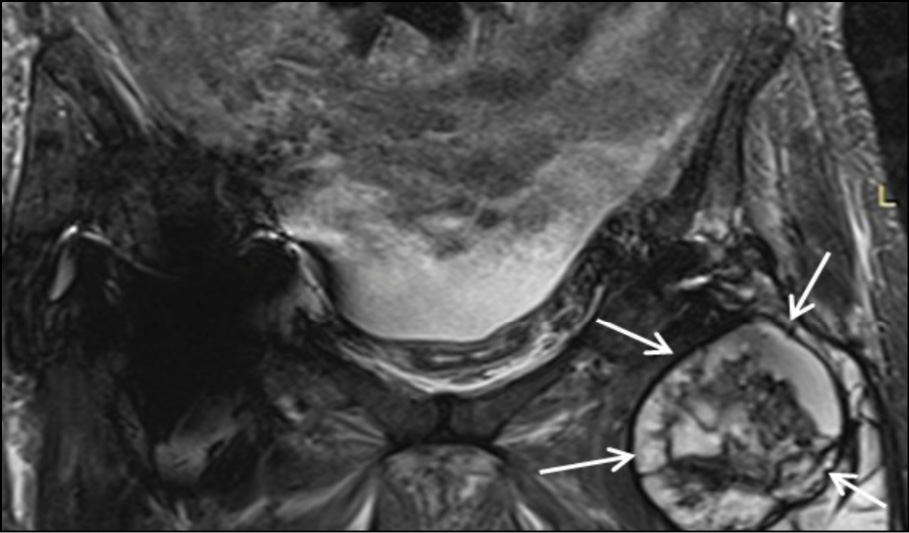

The collection exhibited heterogeneous content, peripheral enhancement, as well as solid-enhancing wall components (Figure 2c-2d). Moreover, bilateral myositis was noted in the upper thigh muscle groups, with abscess formation in the left rectus femoris and the left vastus lateralis (Figure 2e). These findings suggested the presence of an inflammatory pseudotumor following hip arthroplasty, possibly compounded by systemic bacteremia, as evidenced by a history of cat bite. Fluid accumulation was also evident in the pelvic cavity.

Figure 2c - Coronal T1 post Gd Fat –Suppression image at the level of pubic bone. White arrow shows the peripheral enhancement of the encapsulated collection.

Figure 2d - Axial T1 post Gd Fat –Suppression image at the level of femoral neck. White arrow shows the peripheral enhancement of the encapsulated collection.